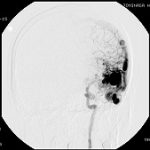

脳血管撮影

手術前

手術後

手術中

モニタリング

手術写真

手術の結果